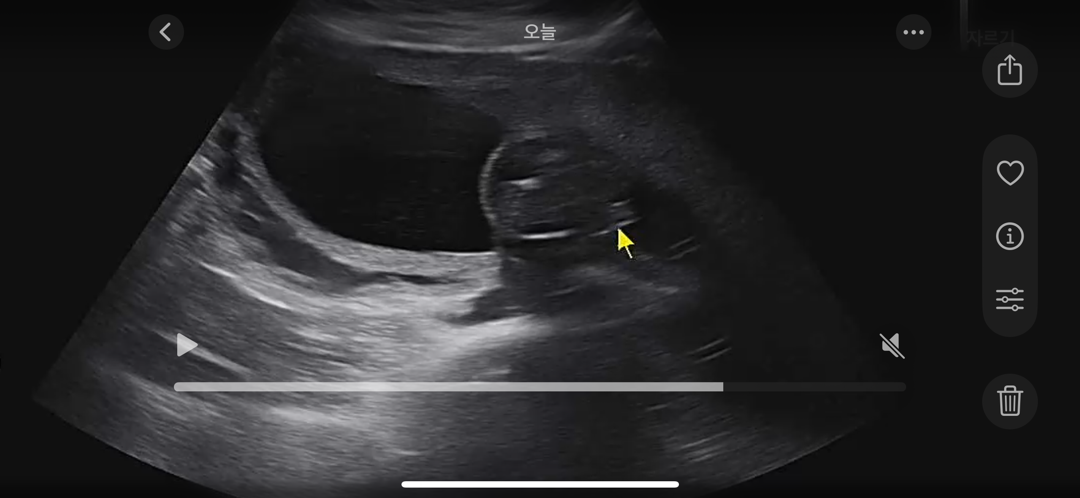

내일이면 20주가 됩니다! 13주때 초음파 사진을 올리고 아들인 것 같다는 댓글들을 달아주셨는데요..! 16주 진료때는 발로 그부분을 가리고 있어서 성별 확인을 못하고 오늘 제 컨디션 이슈로 다른 선생님께 급하게 초음파를 봤는데 다리 사이에 보이는게 작아 딸일 가능성이 높다고 하시네요! 정밀초음파 때 확실히 알 수 있다고는 하는데, 사진처럼 다리 사이에 무언가 작게 보여도 딸일 수 있는 걸까요? 성별 확정받으신 다른 분들의 경험과 의견이 궁금합니다!

소음순 같아요 딸일듯해요

아직까지 잘 안보여서 너무 궁금할것 같아요😂 아들은 14주만 돼도 그냥 나 아들이다! 하고 확실한 존재감을 보여주긴 하더라구요 그냥 확실히 두둥 하고 보였어요 애매하거나 헷갈리는거면 딸이지 않을까요? ㅎㅎ 조심스레 추측해봅니당